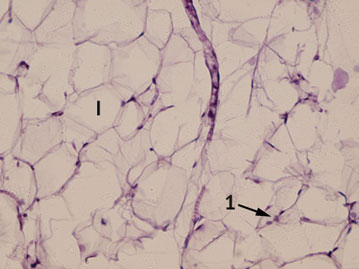

Рис. 3. Париетальная брюшина на 10-е сутки. Окраска гематоксилином и эозином, увеличение ×400: 1 — лейкоциты; I — пограничная базальная мембрана

На 10-е сутки на поверхности брюшины изменений нет, в самой брюшине единичные лейкоциты, которые расценены как вариант нормы (рис. 3).

На 20-е и 30-е сутки брюшина не отличается от нормы. Мезотелиальный слой тонкий, без дефектов, дополнительные фибринозные наложения в виде соединительной ткани отсутствуют (рис. 4).